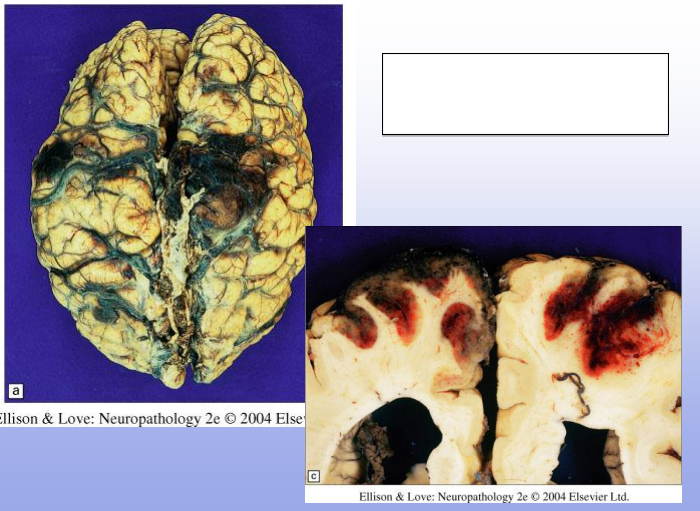

Hemorrhagic Infacts; can be venous (thrombus) or arterial (ischemia and reperfusion)

Venous Infarcts; most commonly seen parasagittally (in superior sagittal sinus distribution) or distribution of transverse sinus

Top: bilateral PCA infarcts from emboli can often become hemorrhagic (and can be multifocal)

Bottom: small clot/embolus (arrow) with surrounding hemorrhagic infarct